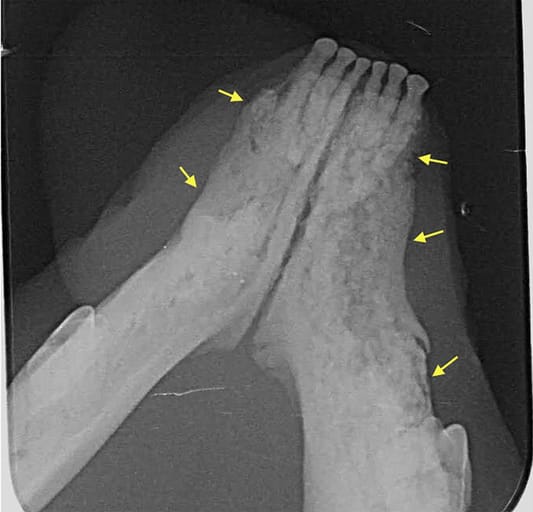

Case 7: Dental radiograph showing ill-defined, irregular shaped, low-dense radiopaque areas located at the most superficial aspect of the affected bone with irregular alveolar bone margins (yellow arrows).